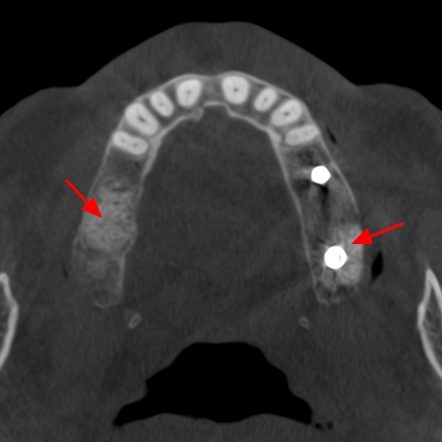

En este contexto, la tomografía computarizada de haz cónico (CBCT) se ha convertido en una herramienta esencial para los profesionales de la odontología. Gracias a la radiología 3D, los especialistas pueden evaluar con exactitud el volumen óseo disponible, identificar estructuras anatómicas importantes (como el nervio dentario o el seno maxilar) y diseñar el tratamiento con la máxima previsión y seguridad.

Para el paciente, esto se traduce en procedimientos más seguros, menos invasivos y con resultados más predecibles. En la fase de seguimiento, el CBCT también permite comprobar la correcta integración del injerto óseo y la evolución del tejido antes de colocar el implante definitivo.